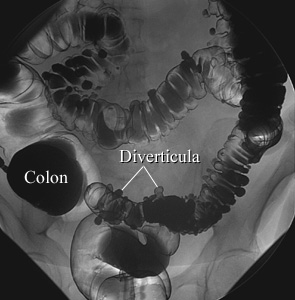

Air-Contrast Barium Enema

Diverticulosis

Courtesy of Intermountain Medical Imaging, Boise, Idaho. All rights reserved.

In an air-contrast study, the colon is first filled with barium and then the barium is drained, leaving only a thin layer of barium on the wall of the colon. The colon is then filled with air. This barium enema image shows pouches (called diverticula) in the wall of the colon.